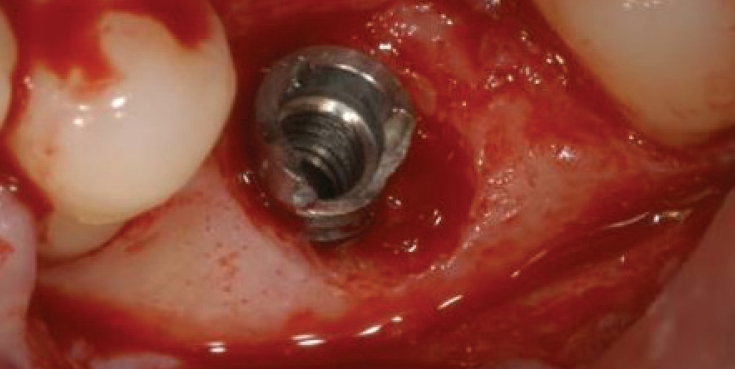

연결나사의 파절보다 빈발하게 발생하는 것이 지대주의 파절인데(Fig. 5) 제거가 잘 되지 않는다. 이때는 다양한 방법으로 제거를 할 수 있으나 최근에는 여러 회사에서 발매되어 나오는 리무버가 있어 제거가 비교적 용이해졌다(Fig. 6).

리무버를 적용할 때 주의할 사항은 역회전으로 고정을 하여야한다는 것이다. 이후에 라쳇이나 토크렌치등으로 잡고 흔들어서 제거해야만 제거가 용이하다. 그럼에도 불구하고 제거에 실패하는 경우에는 bur를 이용하여여 제거하는 수 밖에 없다(Fig. 7).